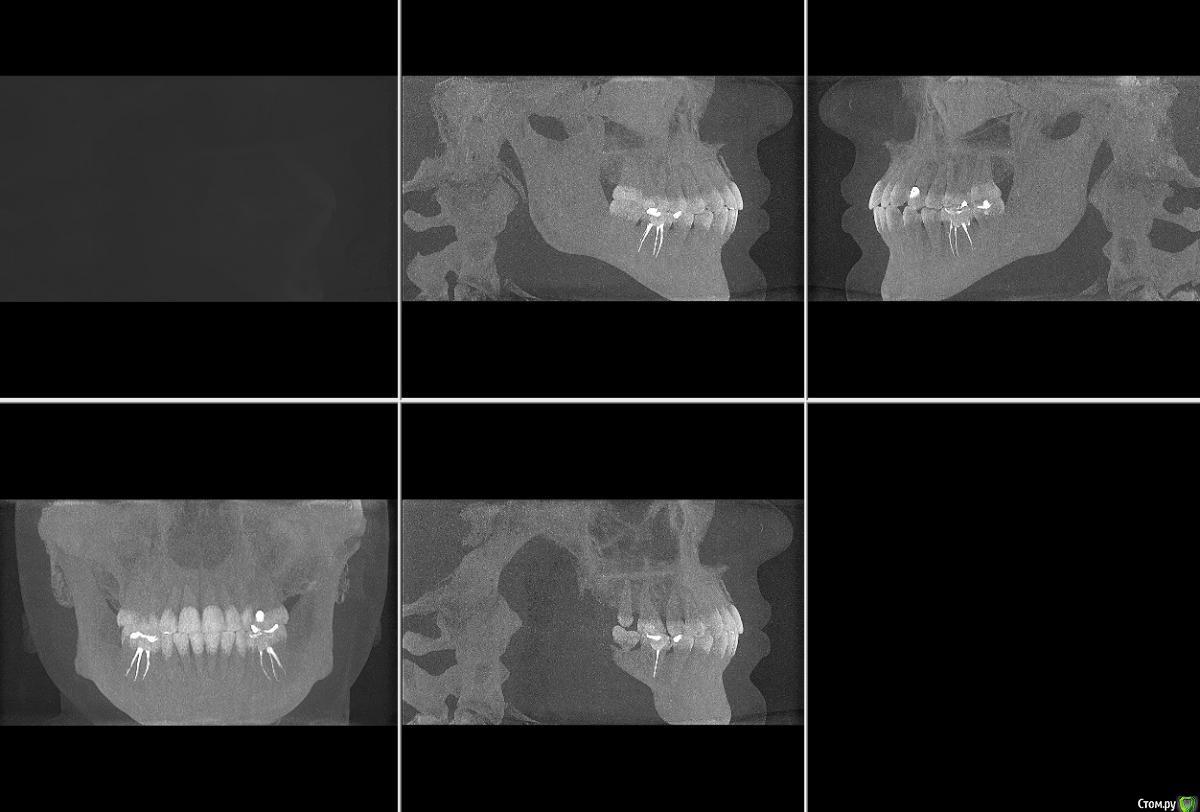

Александр К Опубликовано 8 февраля, 2016 Поделиться Опубликовано 8 февраля, 2016 Добрый день! С супругой произошла неприятность, подскользнулась, получила травму - удар в область передних верхних зубов. Удар был не сильный, даже ни опухоли, ни синяка, ни разбитой губы, но... Шатаеся один зуб уже неделю, чуть болит. После похода в гос и частную клинику совершенно разные вердикты, причем в частной вообще жуть: по томографии врач сказал, что откололась часть кости к которой крепится зуб и теперь его надо удалять, вшивать "новую" кость, ходить пять дней без зуба, потом пол года с элементом вставной челюсти, потом вставлять корень и новый зуб. Все бы ничего, но зуб то вроде целый и для девочки это все ой как не приятно и сложно, да и дорого что тут греха таить.Загуглив я сделал вывод что это перелом альвеолярного отростка верхней челюсти, пишут что установкой шины можно это вылечить. Жалко вот так вот терять здоровый зуб.Теперь о гос поликлинике: врач сделала рентген и указала на перелом корня, хотя врач из частной клиники перелома не увидел. В общем кому верить и что делать не знаем. Пойдем к третьему врачу, но хотелось бы послушать мнение профессионалов со стороны. Буду благодарен любому ответу, спасибо! Ссылка на комментарий

Александр К Опубликовано 8 февраля, 2016 Автор Поделиться Опубликовано 8 февраля, 2016 снимки Ссылка на комментарий